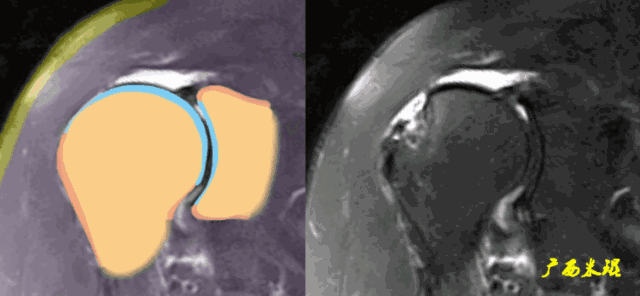

1、斜冠状位:平行于冈上肌腱长轴,主要评估冈上肌。

各个序列肩袖均表现为均匀的低信号,是肌腱的延续。

Grade0:肩袖形态正常,连续性完好,肩袖信号正常。

Grade1:肩袖形态正常,连续性完好,肩袖内信号异常。

Grade2:肩袖连续性存在,形态异常(肩袖变薄/变厚,形态不规则)。

Grade3:肩袖外形异常,连续性中断。

在Zlaikin分级中,0级是正常肩袖,1、2级代表退变,3级为撕裂,也就是真正的肩袖损伤。